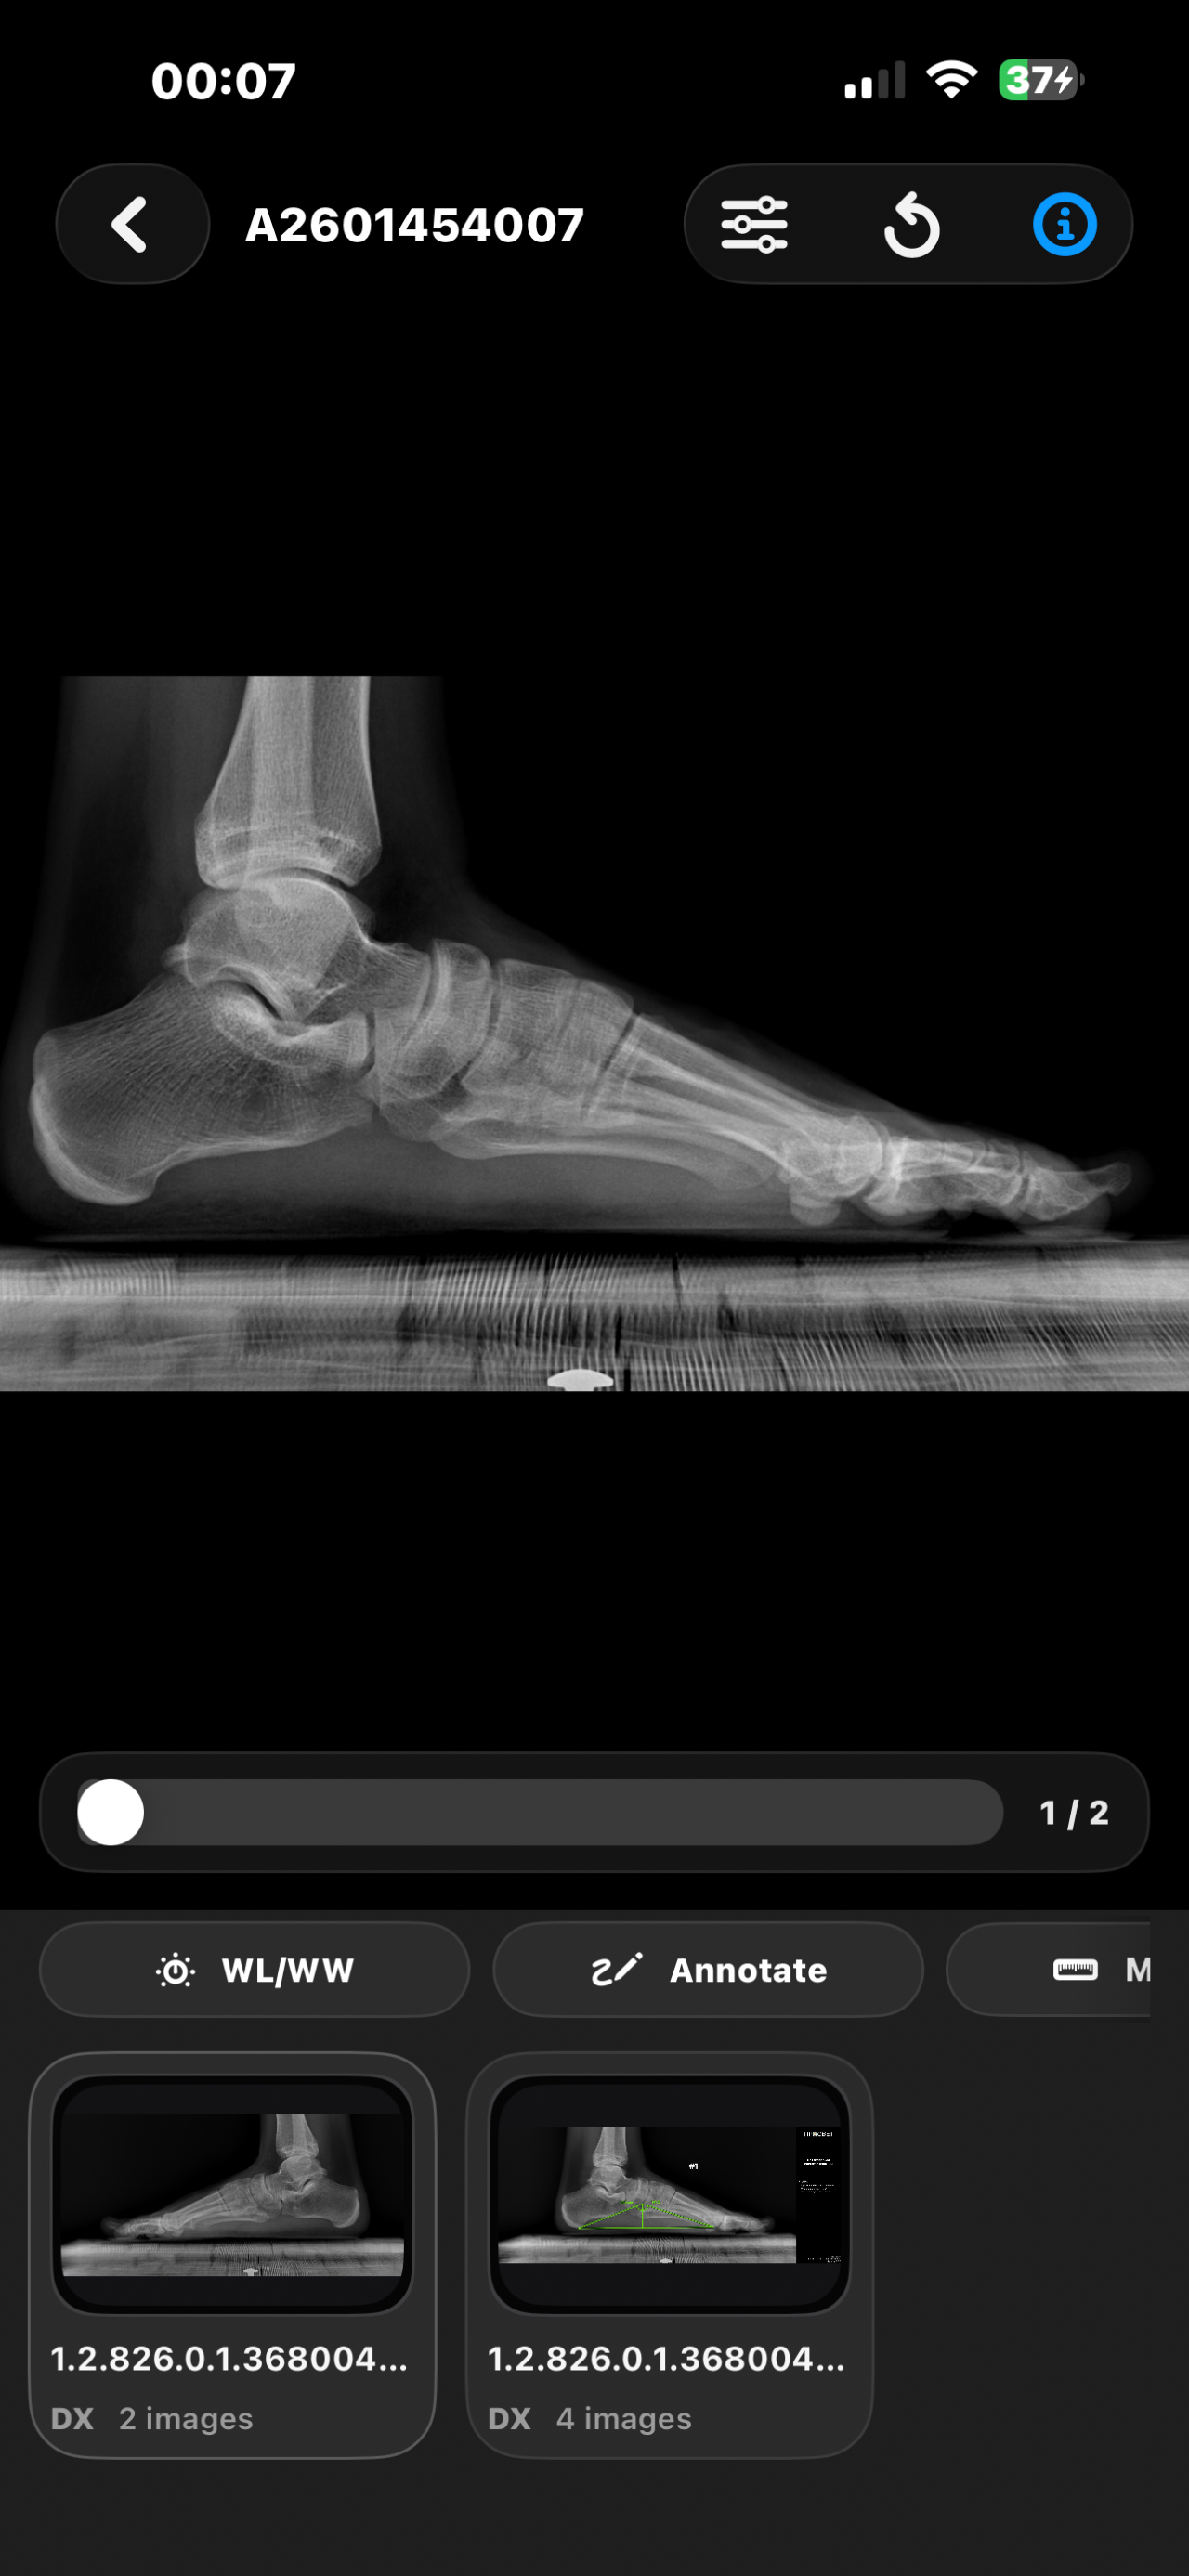

Открыты ли зоны роста. Смогу еще вырасти?

Здравствуйте, мне 16 лет и рост ~173см и мне очень хотелось бы узнать, открыты у меня зоны роста или нет? Сверстники все по 180-185 см и на их фоне я чувствую себя не очень комфортно. Сколько сантиметров я смогу прибавить в росте? Спасибо за ответ!